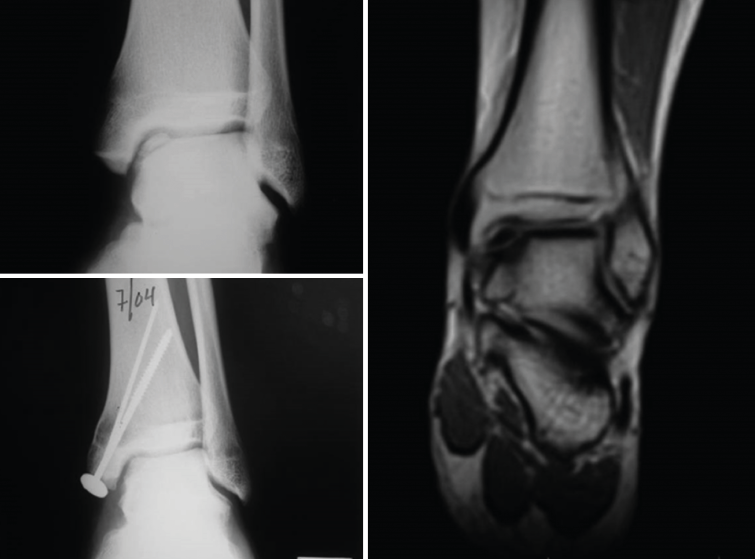

Patients with osteochondral defects of the ankle: results of the first patients with two years of follow-up

A study was made of the first 52 patients with osteochondral defects of the ankle treated with the ICC technique - most of them (34 patients) in the Clínica CEMTRO(35). One of the particularities of the chondrocyte implant procedure in the ankle is that in most cases an osteotomy is first required in order to access the lesion. Although in some patients the defect was more superficial, in the majority of cases (up to 96%) the defect was of an osteochondral nature. In 35% of the patients the lesion was over 4 mm in depth, and a cancellous bone graft was required, obtained from the osteotomy itself, above the subchondral bone, with placement of the membrane with the cells over this graft.

The short/middle term outcomes of the treated patients were very satisfactory. Both pain, evaluated by means of the VAS, and ankle function assessed by the American Orthopedic Foot and Ankle Society (AOFAS) score(36), improved significantly one year after treatment, and this improvement persisted at least one year later. The percentage of patients with good or excellent outcomes after 12 months was 75%, and this figure further increased to 79.2% at 24 months post-treatment.

Figure 19. Cartilage regeneration in the ankle joint after Instant CEMTRO Cell (ICC) treatment. The radiological view shows the appearance of the lesion before and after treatment. The magnetic resonance imaging view 6 months after implantation shows the start of joint cartilage regeneration.

The clinical results were correlated to the radiological findings, revealing correct graft integration and regeneration of the cartilage (Figure 19).